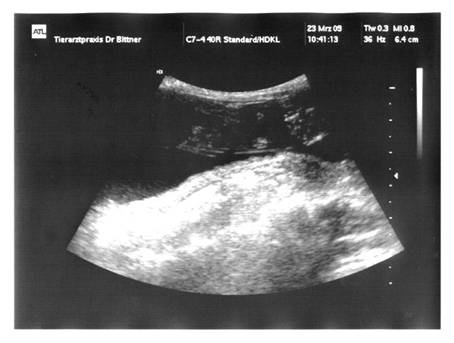

06. 1  1 .2009  Tag 36  |

:  |

MiniFee  |

hatte heute ihren 2. Ultraschall-Termin …

… und der Tierarzt hat

diesmal 2 Babys ganz klar erkannt. Ich

bin so happy, dass MiniFee tragend ist und es ihr,

aber auch ihren Baby’s gut geht

!!!  |